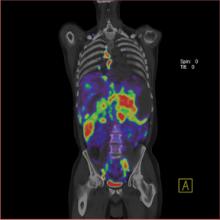

Molecular imaging in clinical trials accelerates the development of promising compounds by allowing physicians to see and assess whether a drug is working as intended for a patient.

Could earlier diagnosis and pre-symptomatic disease detection truly lead to disease prevention? Healthcare is on the cusp of a paradigm shift from a reactionary to a preventative approach to managing disease through diagnostic imaging and radiolabeled probes. So what is holding it back?